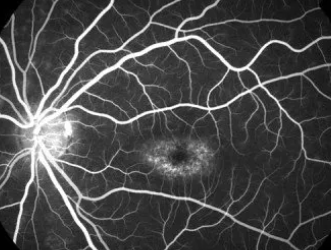

While in high school, I noticed a decline in my vision. Words on the blackboard blurred, and bright light overwhelmed me. Stargardt’s disease is a progressive condition that damages the macula and declines central vision (5,6), which was unknown to my family and most doctors I visited.

My condition was treated as a common refractive error until a visit to a retinal specialist led to advanced imaging and genetic testing. The diagnosis was both a relief and a burden: I finally had a name for my condition, but it came with no cure and a reality of irreversible vision loss. While clinical trials and experimental therapies, such as gene therapy and stem cell treatments, are being explored globally (6), they remain largely inaccessible to patients in India due to high costs and regulatory constraints.